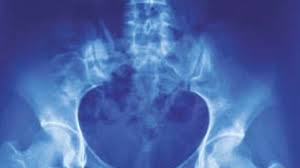

What Are The Symptoms Of Pelvic Bone Cancer : Surgical Management Of Pelvic Primary Bone Tumors Involving The Sacroiliac Joint Sciencedirect - Bone cancer destroys normal bone tissue.. More rarely, the base of the skull is affected. Chondrosarcoma is a cancer that can begin in the bones or tissue near bones, often in the hip, pelvis, and shoulder. Symptoms if cancer has spread to the lymph nodes lymph nodes are part of a system of tubes and glands in the body that filters body fluids and fights infection. The most common locations for chondrosarcoma tumors are in the pelvis, hip and shoulder. Rarely, people with a bone sarcoma may have symptoms such as fever, generally feeling unwell, weight loss, and anemia, which is a low level of red blood cells.

A high temperature (fever) of 38c (100.4f) or above It can spread to distant organs, such as the lungs. Bone cancer is rare, making up less than 1 percent of all cancers. Pelvic bone neoplasms are seldom immediately diagnosed and, therefore, may result in significant morbidity and mortality. Osteosarcoma is probably the most common disease that is related to pelvic bone cancer, with chondrosarcoma following close behind it. Hip pain is a common complaint like that of knee or back pain. At first, the pain is not constant. Bone metastases can weaken your bones and lead to symptoms like bone pain. The bones are the most common place where metastatic breast cancer cells tend to go. Chondrosarcoma is a cancer that can begin in the bones or tissue near bones, often in the hip, pelvis, and shoulder. Symptoms of testicular cancer may include: Can bone cancer be found early? Having too much calcium in your blood , which has numerous causes, is a dangerous condition called.

Bone cancer can begin in any bone in the body, but it most commonly affects the pelvis or the long bones in the arms and legs. There are many pelvic cancer symptoms a person can experience. Bone cancer develops in the skeletal system and destroys tissue. The symptoms of bone cancer are: In contrast, some other metastatic tumors, such as those from the prostate, are commonly osteoblastic, meaning that they form new bone and increase the brittleness of the bones. Rarely, people with a bone sarcoma may have symptoms such as fever, generally feeling unwell, weight loss, and anemia, which is a low level of red blood cells. Although breast cancer can spread to any bone, the most common sites are the ribs, spine, pelvis, and long bones in the arms and legs. Osteosarcoma is probably the most common disease that is related to pelvic bone cancer, with chondrosarcoma following close behind it. A primary bone cancer is one that starts from bone. Although less often, other areas (such as the ribs) may be affected. Can bone cancer be found early? Hip pain is a common complaint like that of knee or back pain. Get the latest health information from mayo clinic delivered to your inbox.